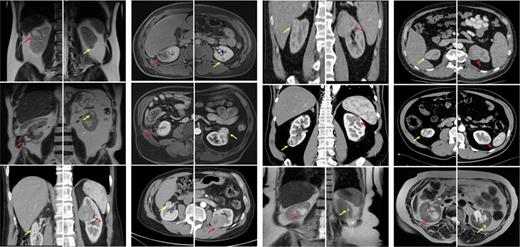

Each patient received OPN on one side and RAPN on the contralateral side. Representative images of all the tumors are shown in Figure 1. The median age was 65 (55–75) years and the cohort included 1 female (17%). The median body mass index was 27 (23.4–30.2) kg/m2 and the median abdominal circumference was 93.7 (87.6–103.6) cm. The time between the two surgeries was 1.8 (1.3–7.2) months, with OPN performed before RAPN in all patients. One major complication (Clavien-Dindo 3) occurred in the OPN group, and none occurred in the RAPN group. One patient treated with OPN for a RENAL 8p kidney tumor experienced postoperative urinoma. After insufficient clinical improvement after drainage, ureteral stenting, and i.v.-antibiotics, revision surgery was performed. Tumors with greater complexity were more often treated with OPN (median RENAL score OPN 8 vs. 6 RAPN). This aligns with our surgical strategy of treating more complex tumors first, typically with OPN, to ensure nephron-sparing. In 2 patients with identical RENAL scores for both sides (8a and 8p), the decision for the surgical strategy was made based on the complexity-by-score, individual preference, and other patient-specific anatomical considerations. Hospitalization duration was longer after OPN (7 days) vs. RAPN (5 days) and ischemia time for OPN was 10 min vs. 5 min for RAPN. There was no difference in the dynamics of postoperative kidney function between the two cohorts. The predominant histologic subtype was clear-cell renal cell carcinoma. There was a greater proportion of T1b tumors in the OPN group; the RAPN group consisted solely of T1a tumors. No patients had a positive nodal status or distant metastases. The surgical and oncologic characteristics of our cohort are shown in Table 1.